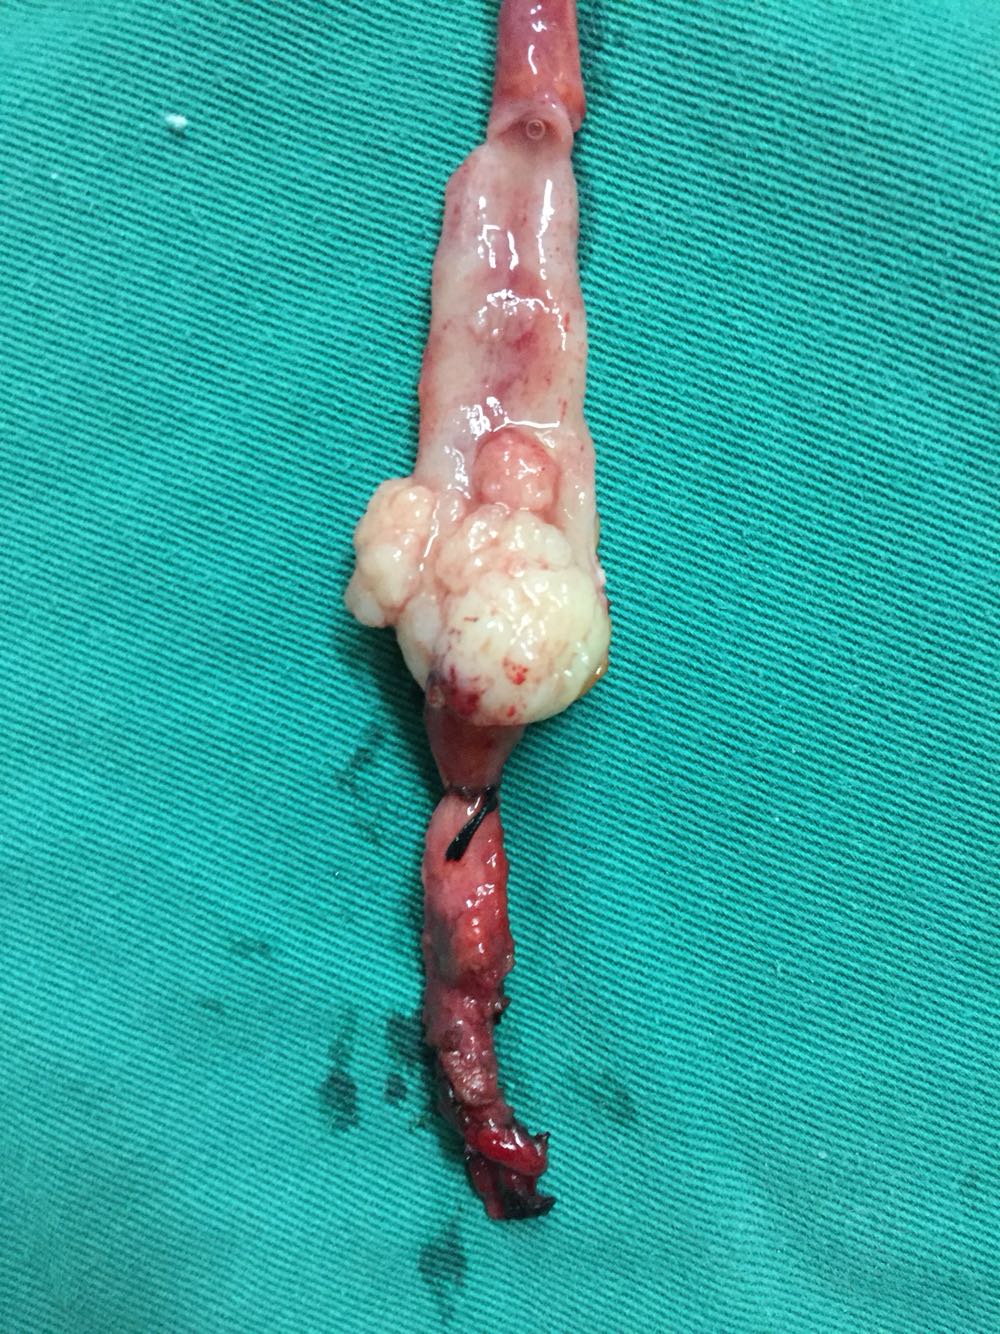

右侧输尿管下段癌,行后腹腔镜下右侧输尿管癌根治性切除术